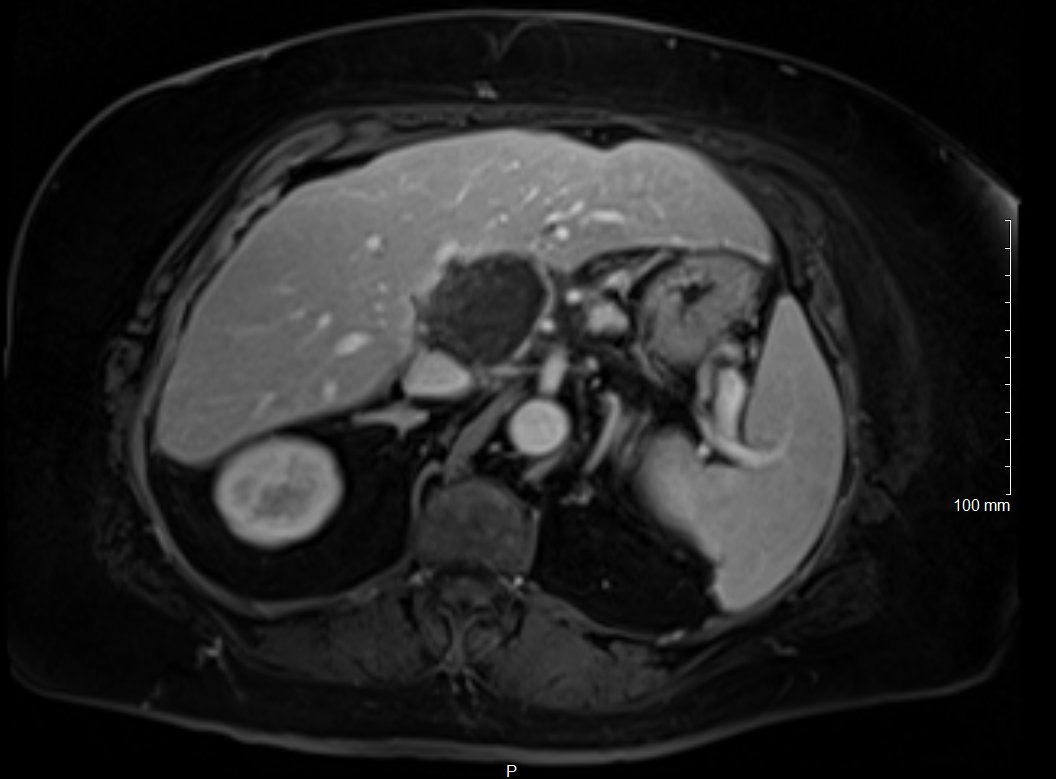

New study @AnnalsofIM bit.ly/2Km3KYu by @DrTalenfeld @WeillCornell: Percutaneous ablation for T1a #renalcancer has similar 5-year survival rates to radical nephrectomy but with far fewer 30-day complications and less #kidneyfailure.